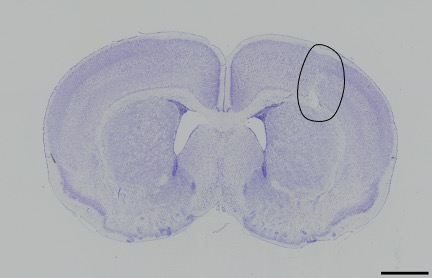

For the preterm infant, the provision of diagnostic measurements of brain compromise is a high priority, in order to minimise the risk of developmental impairment. Amplitude-integrated electroencephalography (aEEG) is used to monitor the functional status of the brain and to observe maturational changes during extrauterine development. Near-infrared spectroscopy (NIRS) enables continuous estimation of cerebral oxygenation. General movements (GM) are part of the spontaneous movement repertoire of newborn infants. The presence, quality and intensity of GM are markers of central nervous system integrity. Quality of GM has emerged as a reliable predictor of neurodevelopmental delay in preterm infants. Cerebral magnetic resonance imaging (MRI), performed at term-equivalent age in all very preterm infants, provides detailed information on the wide spectrum of preterm brain injury and alterations in postnatal brain development in preterm infants (Fig. 1).

Our research laboratory focuses on the evaluation of potential neuroprotective drugs in different in vivo and in vitro models to counteract newborn brain injury (Fig. 2). One current focus is on evaluation of the therapeutic potential of endogenous sigma-1 receptor ligands, such as dehydroepiandrosterone and its sulphate ester, and of levomepromazine, a phenothiazine neuroleptic drug with strong analgesic and sedative properties.